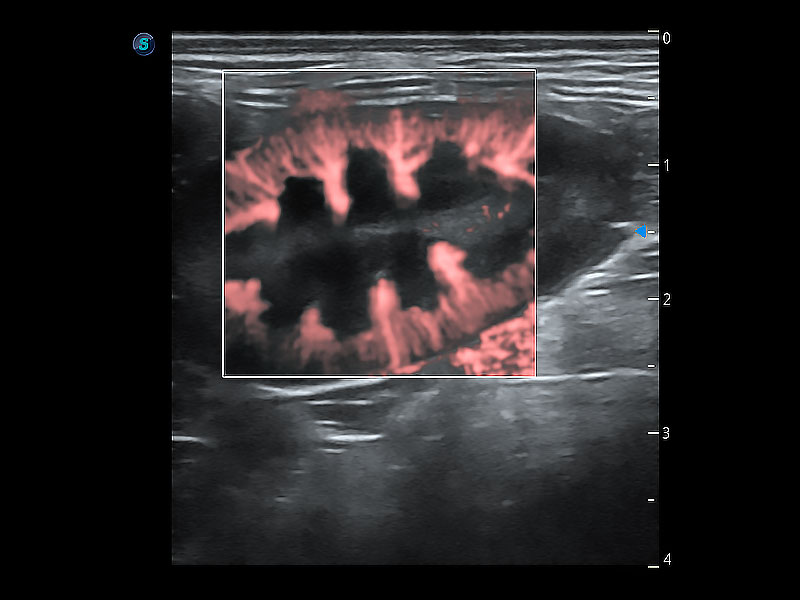

实时用颜色表示心肌组织运动,观察和定量组织的运动情況,对快速检测与评估心肌的灌注和活性、电传导及心肌收缩和舒张功能等均能提供重要的诊断信息。